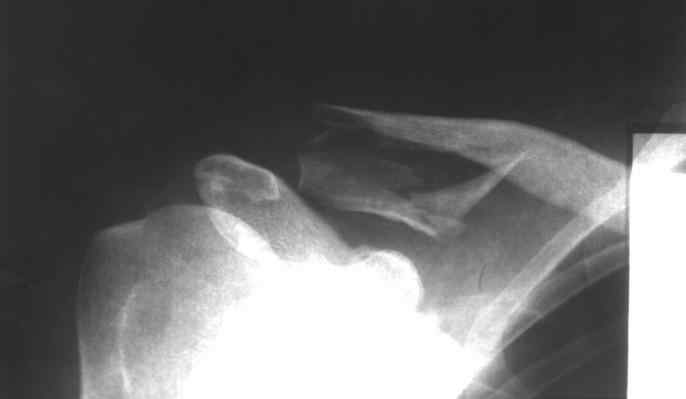

Пациент,32 года, травма - падение с высоты на правое плечо. Прооперирован 20.05.08.... Ad oculus, при ревизии перелома, многооскольчатый перелом, акромиально-ключичное сочленение сохранено. Коллеги, прошу высказать ваше мнение по поводу данного случая: Выбор метода? качество остеосинтеза? ваш вариант лечения? Возможные осложнения? Спасибо!

Здесь чистый перелом ключицы, который прекрасно срастается без операции. А связки AKC целы. Хотя такое повреждение можно лечить как повреждение АКС. Например, аппаратом. Презентация на эту тему лежит тут (4,7 Mb).

Не согласен. Лечить без операции, конечно. можно, но переломы ДИСТАЛЬНОГО отдела ключицы дают очень высокий процент несращений, потому все-таки страндартная рекомнедация - оперировать. можно лентой, спицами чрезсуставно, пластинами - как угодно

Плохо срастался бы "короткий" перелом с отрывом связок или сразу медиальнее их. А такой, как здесь, с горизонтальным раскалыванием дистального конца ключицы, имеет большую площадь излома, соответственно, и костеобразования. Ни разу не встречал несращения при подобном по форме переломе.